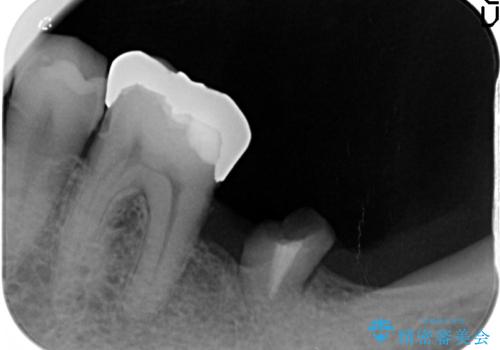

今回、左下6は頬側歯頚部に虫歯があり圧下を行ったことからクラウンにより補綴を行いました。